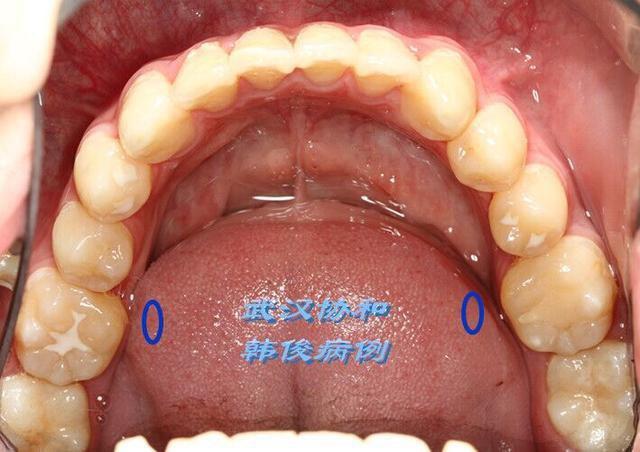

怎么判断孩子有蛔虫?

宝宝肚里有虫,可能出现的症状有肛门处总是痒痒或是频繁肚子疼,不过,这也并不是绝对的!

最直接的证据只有两种:亲眼所见or化验大便!